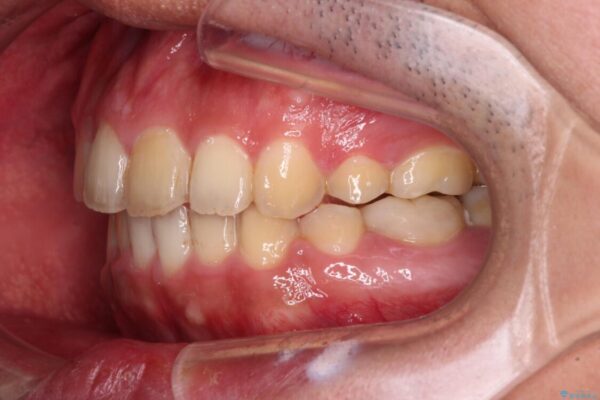

治療前

• 後戻りでデコボコの前歯 インビザライン矯正治療 治療前画像